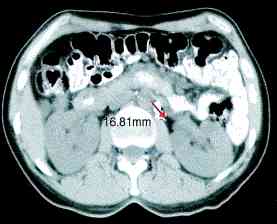

cervix ports, the node positions on CT scans (IJROBP

2002;54:1147) (A) Furthest

distance from lymph node to vessel wall. (B)

Para-aortic lymph node CTV. (C)

Common iliac lymph node CTV. (D)

External iliac CTV, including lateral group. (E) External

iliac CTV, including medial (obturator) group. (F)

Inguinal lymph node CTV. CTV depicted by thick orange line.

Small bowel demarcated by thin magenta, large bowel by thin

blue, rectum by thin dark purple, bladder by thin turquoise, and

uterus by thin yellow-green line. RTOG atlas